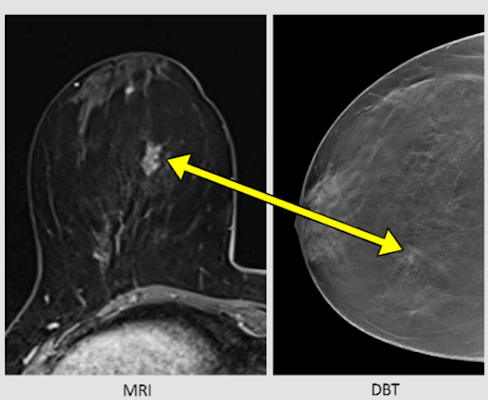

(A) Examples of B-mode images for the measurement of membrane thickness of implants from each of the four types of implants. Images are presented at the same scale. Membrane thicknesses (B) and then shear moduli measured by ARFI method (C) are compared without dissociation as a function of prosthesis age or implantation time. (NS: p-value > 0.05, *: p-value < 0.05, **: p-value < 0.01, ***: p-value < 0.001). Images are available for republishing under a Creative Commons license (CC BY-NC-ND 4.0 Deed) and courtesy of the Journal of Biomechanics.